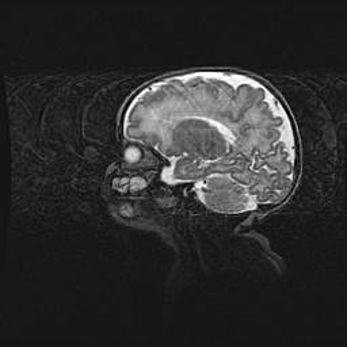

Сообщающаяся гидроцефалия. Кистозная энцефаломаляция головного мозга.

Возраст: 3 месяца 4 дня

Вес: 3100 г

Пол: женский

Окружность головы: 34 см

Срок гестации: 31 неделя

Кистозная энцефаломаляция головного мозга - одна из форм поражения головного мозга в детском возрасте. Характеризуется возникновением множественных и распространённых кист в коре, белом веществе и подкорковых образованиях головного мозга у плодов, новорождённых и детей раннего возраста. Развитие кистозной энцефаломаляции связано с внутриутробной асфиксией и гипотонией, родовой травмой, тромбозом синусов, пороками развития сосудов, инфекциями, сепсисом и другими причинами. Наиболее значимые инфекционные агенты: вирусы простого герпеса, цитомегалии, краснухи, токсоплазмы, энтеробактерии, золотистый стафилококк и другие.